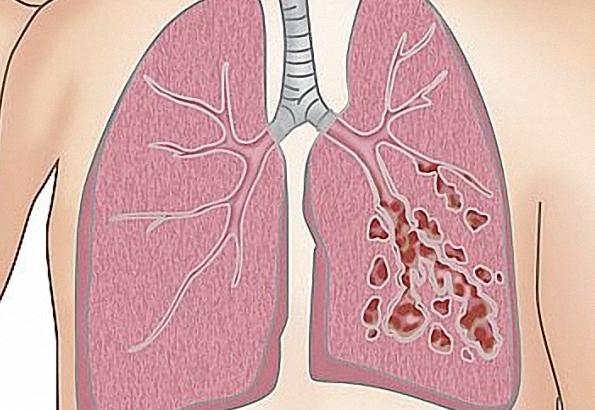

支气管扩张是指支气管树的异常扩张,是一种呼吸道的慢性化脓性炎症。反复发作的慢性炎症和纤维沉积或纤维化修复使支气管壁毁损,导致支气管持久扩张、变形,且这一过程是不可逆的。支气管扩张不是一种独立的疾病,多种直接或间接导致支气管壁受损的疾病均可导致支气管扩张。支气管扩张可称弥散性,也可仅有一两处病灶,一般支气管扩张多发生于中等大小的支气管,更细小的支气管则最终闭塞。

支气管扩张部位的支气管壁存在慢性炎症而遭到破坏,纤毛细胞受损或消失,粘液分泌增多。此外,支气管壁的正常张力丧失:受累支气管变得更大而松弛,向外突出,或形成囊状。粘液分泌增多有利于细菌滋生,常可阻塞支气管,导致感染性分泌物积聚而进一步损害支气管壁。炎症亦可扩展至肺泡,引起支气管肺炎,瘢痕形成,以及具有功能的肺组织减少。严重患者,肺内瘢痕形成和血管减少最终可加重心脏负担。此外,支气管壁的炎症和血管增多又可引起咯血。受累的气道闭塞将导致血氧含量异常降低。